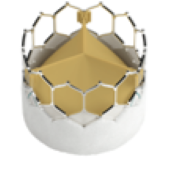

TAVIは、カテーテルに装填された人工弁を、狭窄して機能不全におちいった自己弁の上に拡張し留置します。当院では、風船拡張の手法で留置する人工弁1種類と形状記憶の特性を生かした自己拡張能を有する人工弁の2種類を用いています。鼡径部の大腿動脈から挿入する経大腿動脈アプローチ法、胸の皮膚の小さな切開から心臓の先の心尖部の動きの少ない部位に挿入する経心尖部アプローチ法、他に鎖骨下動脈や胸部大動脈を経由したアプローチ法が、事前にえられた画像情報により、ハートチームにおける検討のもと、適正に選択されます。

TAVIは、カテーテルに装填された人工弁を、狭窄して機能不全におちいった自己弁の上に拡張し留置します。当院では、風船拡張の手法で留置する人工弁1種類と形状記憶の特性を生かした自己拡張能を有する人工弁の2種類を用いています。鼡径部の大腿動脈から挿入する経大腿動脈アプローチ法、胸の皮膚の小さな切開から心臓の先の心尖部の動きの少ない部位に挿入する経心尖部アプローチ法、他に鎖骨下動脈や胸部大動脈を経由したアプローチ法が、事前にえられた画像情報により、ハートチームにおける検討のもと、適正に選択されます。

バルーン拡張型人工弁

自己拡張型人工弁